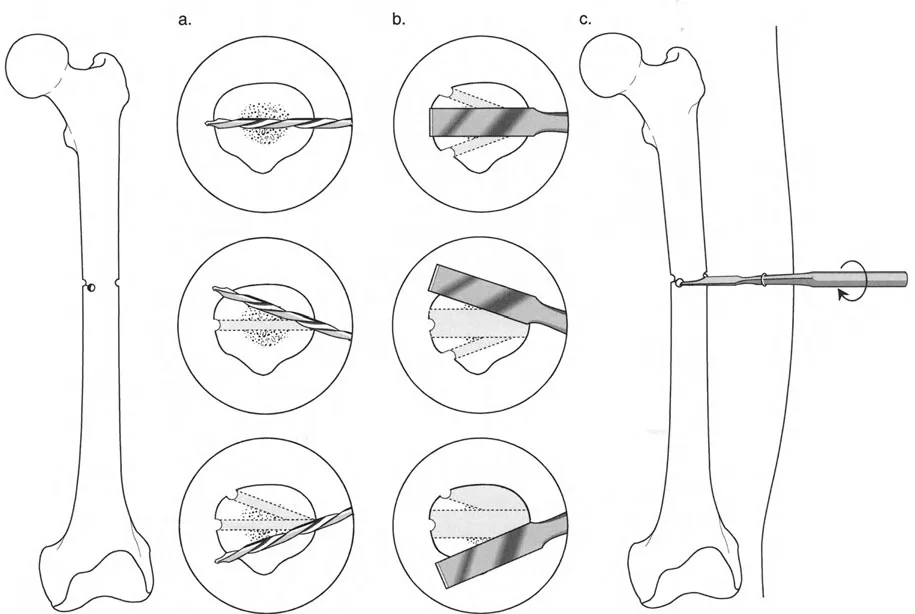

فهم قواعد بالي لقطع العظم أمر لا غنى عنه لتخطيط الإطار:

- قاعدة قطع العظم 1: عندما يمر قطع العظم ومحور تصحيح الانحراف (ACA) كلاهما عبر مركز دوران الانحراف (CORA)، فإن نهايات العظم ستنحرف دون ترجمة (انزياح). يتم استعادة المحور الميكانيكي، وتظل نهايات العظم متقاربة تمامًا، مما يخلق تصحيحًا كلاسيكيًا "إسفينيًا مفتوحًا" أو "إسفينيًا مغلقًا".

- قاعدة قطع العظم 2: عندما يمر محور تصحيح الانحراف (ACA) عبر مركز دوران الانحراف (CORA)، ولكن يتم إجراء قطع العظم على مستوى مختلف (غالبًا بسبب ضعف جودة العظم عند CORA أو مشاكل في الجلد)، فإن نهايات العظم ستنحرف وتخضع لترجمة محسوبة ومقصودة لإعادة محاذاة المحور الميكانيكي.

- قاعدة قطع العظم 3: (للاكمال) عندما يمر قطع العظم عبر مركز دوران الانحراف (CORA)، ولكن يتم وضع محور تصحيح الانحراف (ACA) خارج CORA، سيتم إنشاء تشوه ترجمة جديد، وهو خطأ شائع في وضع المفصلات غير المخطط له جيدًا.

في المنشآت القريبة من المفصل، غالبًا ما نعتمد على قاعدة قطع العظم 2. نظرًا لأنه لا يمكننا قطع العظم بأمان عند خط المفصل تمامًا (مركز دوران الانحراف CORA)، فإننا نقطع العظم في مستوى أدنى في منطقة الميتافيسيس. بعد تحقيق التصحيح الزاوي عبر المفصلات (محور تصحيح الانحراف ACA)، يتم إعادة محاذاة خطوط المحور الميكانيكي بشكل مثالي، ولكن نهايات العظم في موقع قطع العظم تتحرك بالنسبة لبعضها البعض.